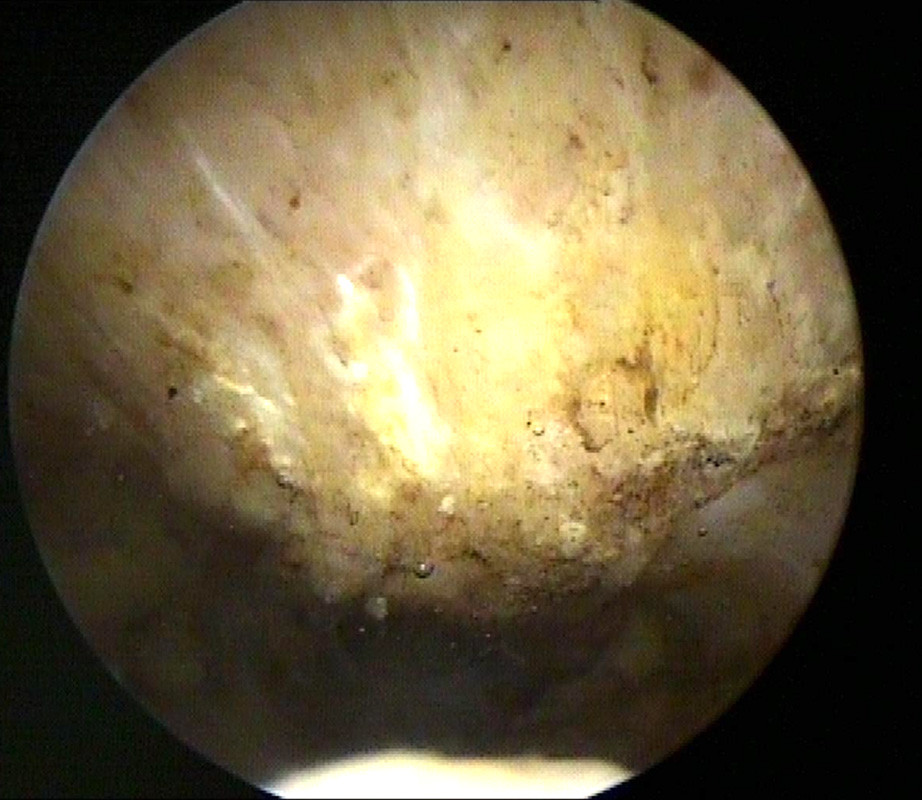

Während der Arthroskopie wird die ganze Schulter von innen untersucht und Knorpel, Sehnen, Schleimhaut, Bänder und eben auch der Knochensporn dargestellt. Der Knochensporn liegt nicht direkt in der Schulter, sondern über der Rotatorenmanschette. Um Ihn gut zu sehen muss meistens vorher der entzündete Schleimbeutel entfernt werden.

Das Bild links zeigt den nach unter ragenden Knochensporn, das Bild rechts zeigt die unter dem Knochensporn aufgeriebene Sehne und ein Operationsinstrument). Dieser Knochensporn wird dann zunächst von den Weichgeweben befreit und mit dann abgetragen, damit die Unterfläche des Schulterdaches dann glatt und eben ist.